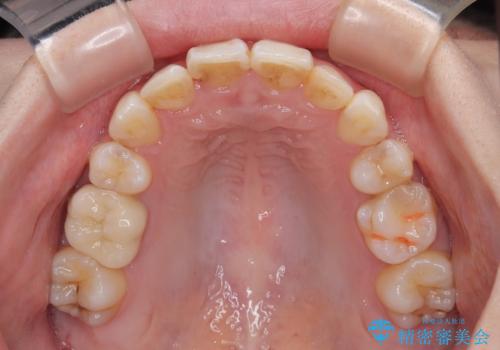

- 前歯のデコボコを気にして来院された患者様です。

上下の前歯にデコボコがあり、更にはディープバイトにより下顎前歯の大半が隠れている状態でした。

上顎左右第一小臼歯の2本を抜歯し、ワイヤー装置を使用して咬み合わせ高さを改善しながら、歯列を整えて行くこととしました。